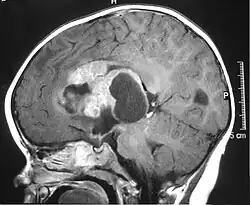

| MRI of an AT/RT | |

- Magnetic resonance imaging (MRI) of the brain and spine

The initial diagnosis of a tumor is made with a radiographic study (MRI[28] or CT-). If CT was performed first, an MRI is usually performed as the images are often more detailed and may reveal previously undetected metastatic tumors in other locations of the brain. In addition, an MRI of the spine is usually performed. The AT/RT tumor often spreads to the spine. AT/RT is difficult to diagnose only from radiographic study; usually, a pathologist must perform a cytological or genetic analysis.

The tumors' appearance on CT and MRI are not specific, tending towards large size, calcifications, necrosis (tissue death), and hemorrhage (bleeding). Radiological studies alone cannot identify AT/RT; a pathologist almost always has to evaluate a brain tissue sample.

The increased cellularity of the tumor may make the appearance on an uncontrasted CT to have increased attenuation. Solid parts of the tumor often enhance with contrast MRI finding on T1 and T2 weighted images are variable. Precontrast T2 weighted images may show an isosignal or slightly hypersignal. Solid components of the tumor may enhance with contrast, but not always. MRI studies appear to be more able to pick up metastatic foci in other intracranial locations, as well as intraspinal locations.